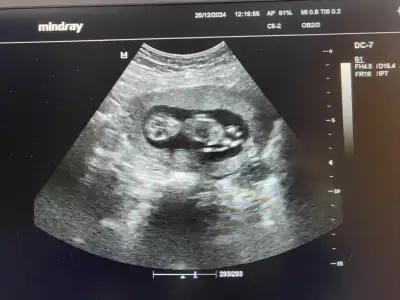

Tahmin var mı ? 😄

Eklentiler

• IMG_3913.webp

IMG_3913.webp

37,8 KB · Görüntüleme: 91